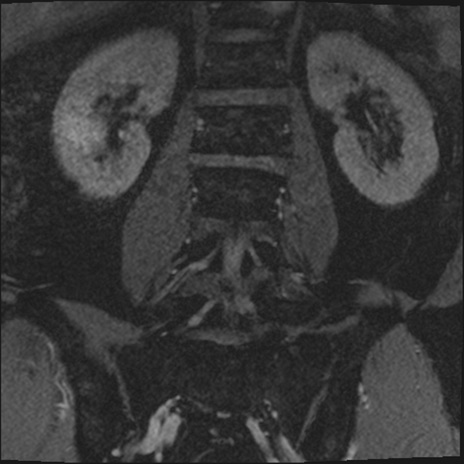

【整形】TIPS症例2 腰椎MRI 3D(冠状断像)

【症例】70歳代男性

【主訴】左下肢痛

【現病歴】2週間前くらいから腰痛、左下肢痛あり。左臀部から大腿、下腿外側のしびれが常時ある。歩行とともに同部位の痛みあり。

【身体所見】Lasegue70-/60+、Bragard-/±、PTR ±/±、ATR -/-、IP 5/5、TA 5/4、TS 5/5、EHL 右第1足趾なし/3、FHL 5/5、hypersthesia(-)、足背動脈触知良好

異常所見と診断は?